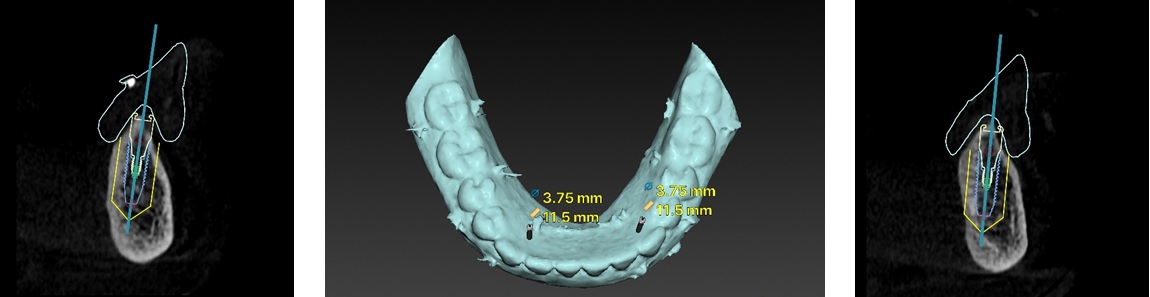

インプラント手術後の

レントゲン写真

インプラント手術後のレントゲン写真ですが、計画した通りの位置にインプラントを埋入することができました。